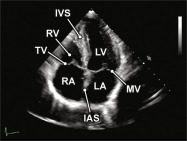

| 2.14. Mặt cắt 4 buồng từ mỏm |

||||||||

|

|

Cửa sổ siêu âm từ mỏm tim Mặt cắt 4 buồng

Bệnh nhân nằm nghiêng trái, xác định diện đập của mỏm tim, marker đầu dò hướng về giường bệnh |

Nhĩ trái (LA)

Van hai lá (MV) Thất trái (LV) Vách liên thất (IVS) Thất phải (RV) Van ba lá (TV) Nhĩ phải (RA) Vách liên nhĩ (IAS) |